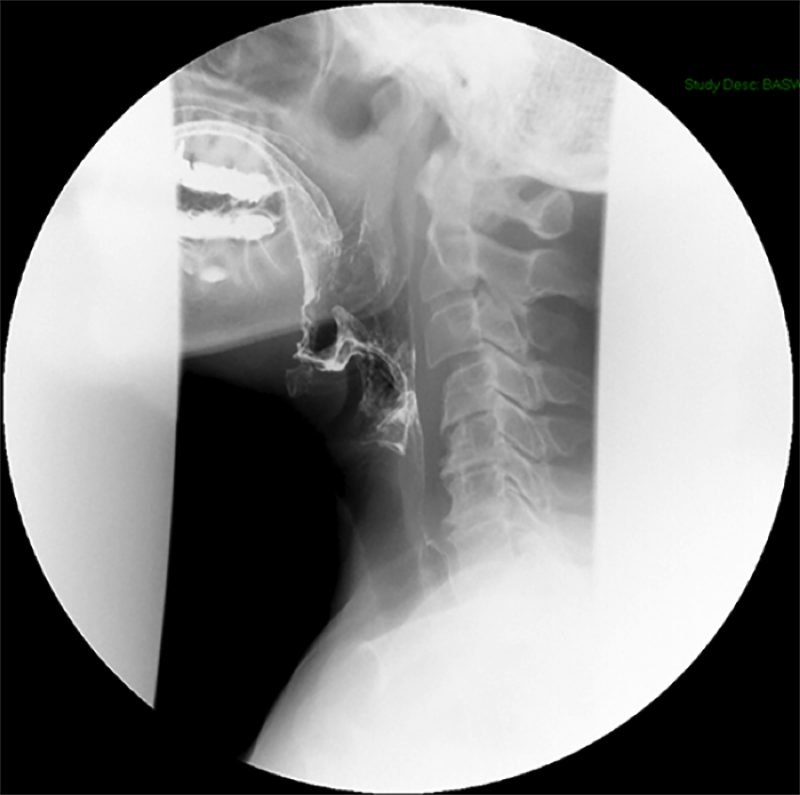

- Method—Cervical:

- Start with the patient in the upright lateral position.

- Ensure the fluoro machine is set to 4 images per second (rapid sequence).

- Explain to the patient that you are going to have them take a "comfortable mouthful" of barium and that they will need to hold it in their mouths until you count to 3.

- Make sure they understand that they are not to swallow until the count of 3.

- Once the patient has taken the "comfortable mouthful" of barium, center the fluoroscope on the cervical esophagus.

- Once the fluoroscope is properly positioned, begin counting. On the count of 2, begin taking rapid sequence images of the contrast material bolus as it moves through the cervical esophagus

(key image 1)

- Take the fluoroscope off rapid sequence.

- With the patient in the lateral position, obtain a spot film of the pharynx and cervical esophagus while they phonate the letter "e"

(key image 2).

- Repeat steps 4-7 with the patient in the AP position

(key image 3)

(key image 4).

- Cervical images are obtained in the lateral and AP projections as the patient swallows thick barium.

- Cervical image are obtained using rapid sequence fluoroscopic spot films at a rate of 4 frames per second.

- To time this appropriately, you will count to 3. You will begin to take images on 2, the patient will swallow on 3.